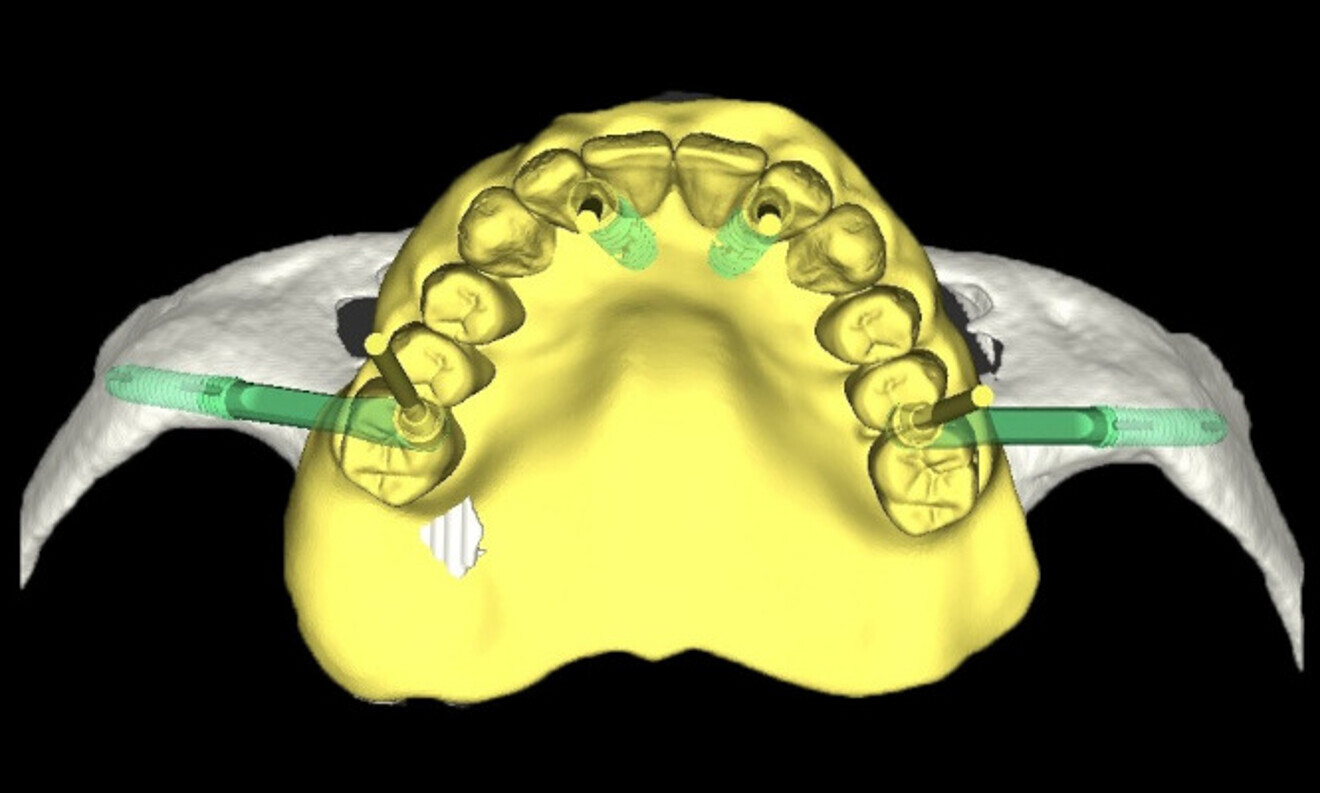

CoDiagnostiX software (Dental Wings) was used for planning the analogue surgical placement of two Straumann zygomatic implants and two Straumann BLX implants in the maxilla and of four Straumann BLX implants in the mandible. The protocol chosen was immediate placement after atraumatic extraction of the remaining teeth while protecting the remaining bone (Figs. 4 & 5). The patient’s STL file was generated and sent to the in-house laboratory to create a 3D-printed model for the surgical planning, allowing us to obtain a surgical model (Fig. 6).